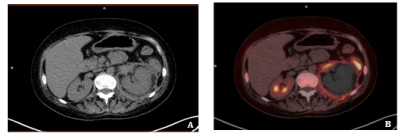

After 12 months of follow up, she remains stable in last 18F-FDG PET-CT study, with a mild clinical improvement (Figure 5).

Figure 5. 18F-FDG PET-CT after 12 months of monitoring. After amphotericine B and isavuconazole therapy, the patient remains stable with mild clinical improvement